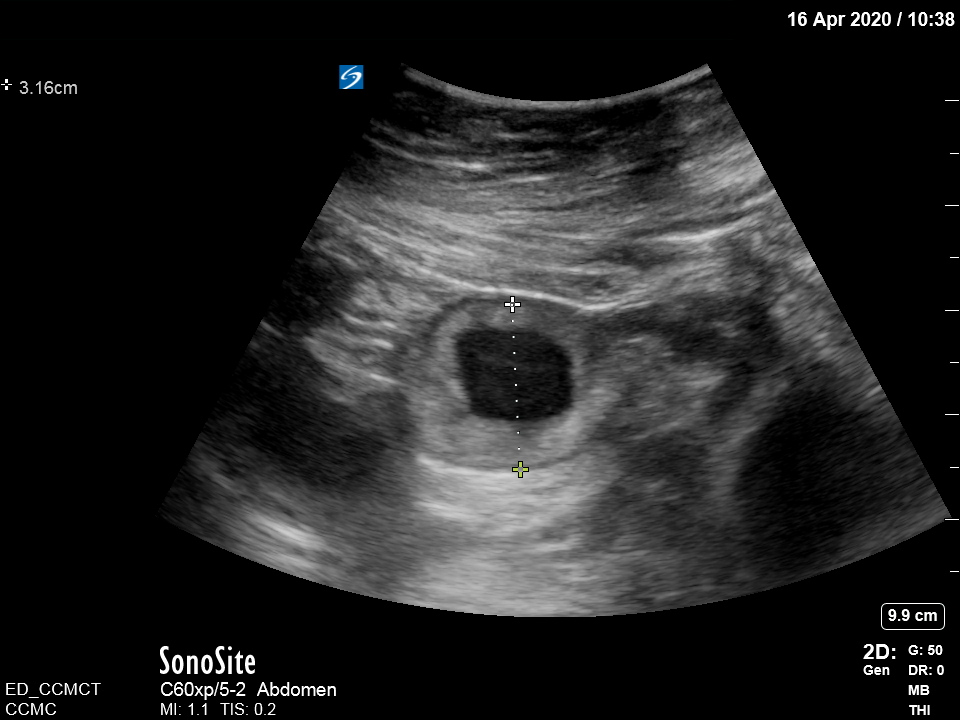

On examination, vital signs were temperature of 98.3º F, pulse of 108 bpm, respiratory rate of 15, blood pressure 146/91 and oxygen saturation of 97% on room air. Significant findings on examination were mild, diffuse tenderness over the abdomen on palpation, which was soft, positive for bowel sounds on auscultation. Bedside ultrasound performed showed keyboard sign – plicae circularis on the interior aspect of the jejunal wall, “to-and-fro” motion, and dilated bowel loops raising suspicion for small bowel obstruction (SBO), which was confirmed by CT.

- Dilated bowel loops with most studies using >25 mm as the cut-off for diagnosis (Figures 1 and 2).

- “Keyboard” sign: visualization of the plicae circularis (Figure 3).